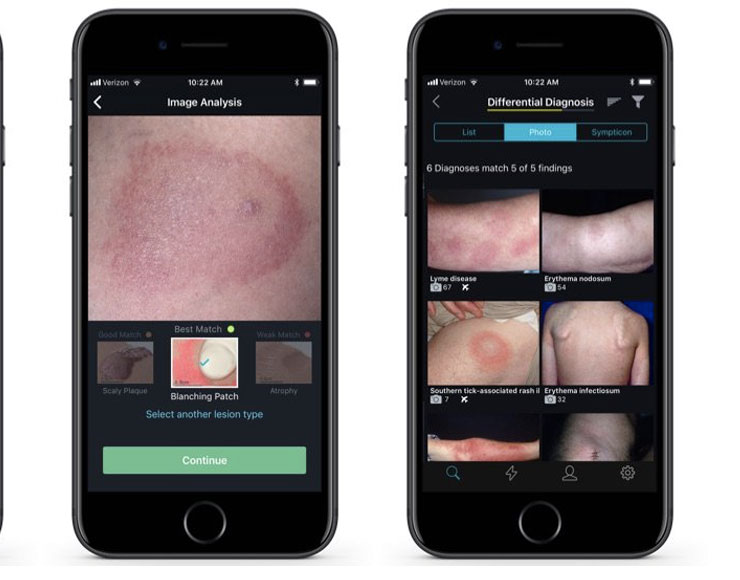

VisualDx, l’app che piace a Tim Cook mostra il futuro della medicina

Di VisualDx ne ha parlato anche Tim Cook: l’app sfrutta la fotocamera di iPhone per riconoscere malattie e disturbi della pelle. Mostra come potrà diventare in futuro la medicina grazie a intelligenza artificiale e apprendimento automatico